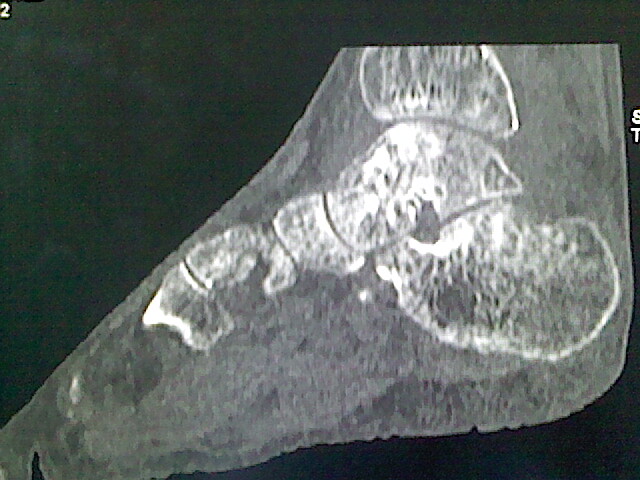

标题: CT16814:男,76岁,左小腿疼痛,不能站立 大家给看看 [打印本页]

男,76岁,左小腿疼痛,不能站立

本例骨质改变主要表现为滑膜或韧带区的骨侵蚀融解(胫腓联合区骨质破坏无硬化边),距骨后部骨质破坏区有硬化边及死骨样改变.所以,本例考虑关节结核可能性大,绒毛膜结节性滑膜炎多发于中年,且极少见于膝髋以外的关节,骨质硬坏也以压陷吸收为主,有明显的硬化边,骨膜增生呈结节状(可以mr鉴别),所以本例暂除外.

另不除外可引起相似表现的其他炎症如布氏杆菌性关节炎等